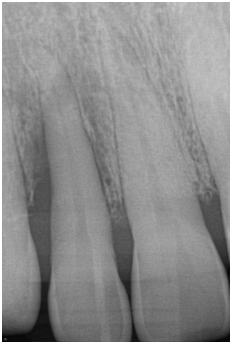

Supportive periodontal therapy was performed for the patient on a regular basis starting 6 weeks after surgery and every three months making sure not to instrument the surgical site subgingivally. The overall plaque control was optimal. The patient was recalled 6 months following surgery. Full-mouth periodontal charting was completed. The disto-palatal surface of tooth #7 exhibited a remarkable reduction in PD, BOP and mobility (Table 1). The patient was pleased with the esthetics and function at this time. A periapical radiograph obtained and demonstrated bone fill in the treated area with a uniform trabecular bone pattern (Figure 3) 12 months follow-up was performed that revealed consistent clinical findings when they were compared with those at 6 months. The disto-palatal surface of tooth #7 exhibited a remarkable reduction in PD to 4mm. There was a CAL gain of 5mm (Figure 4a & 4b). Tables 1 present probing measure at baseline, 6 and 12 months and documents a tendency for continued improvement in PD and CAL. The periapical radiograph at 12 months demonstrates a gain of interproximal bone height in the region between teeth #6 and #7 (Figure 5).

Figure 5 Periapical radiograph of tooth #7 taken 12 months after surgery demonstrated bone fill in the treated area with a uniform trabecular bone pattern.